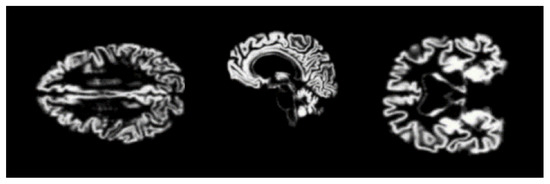

4.2.4. Rescaling

4.2.5. Smoothing

4.2.6. Augmentation